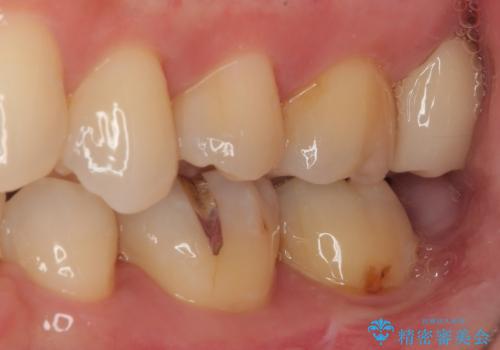

歯列が移動したとはいえ、左右ともに後方傾斜しており、むし歯の除去、形成(形を整える)、型取りの全てが非常に困難な処置となりました。

セラミッククラウンの適合はレントゲン写真からも分かる通り、境界がぴったりと合った、高適合のものとなりました。